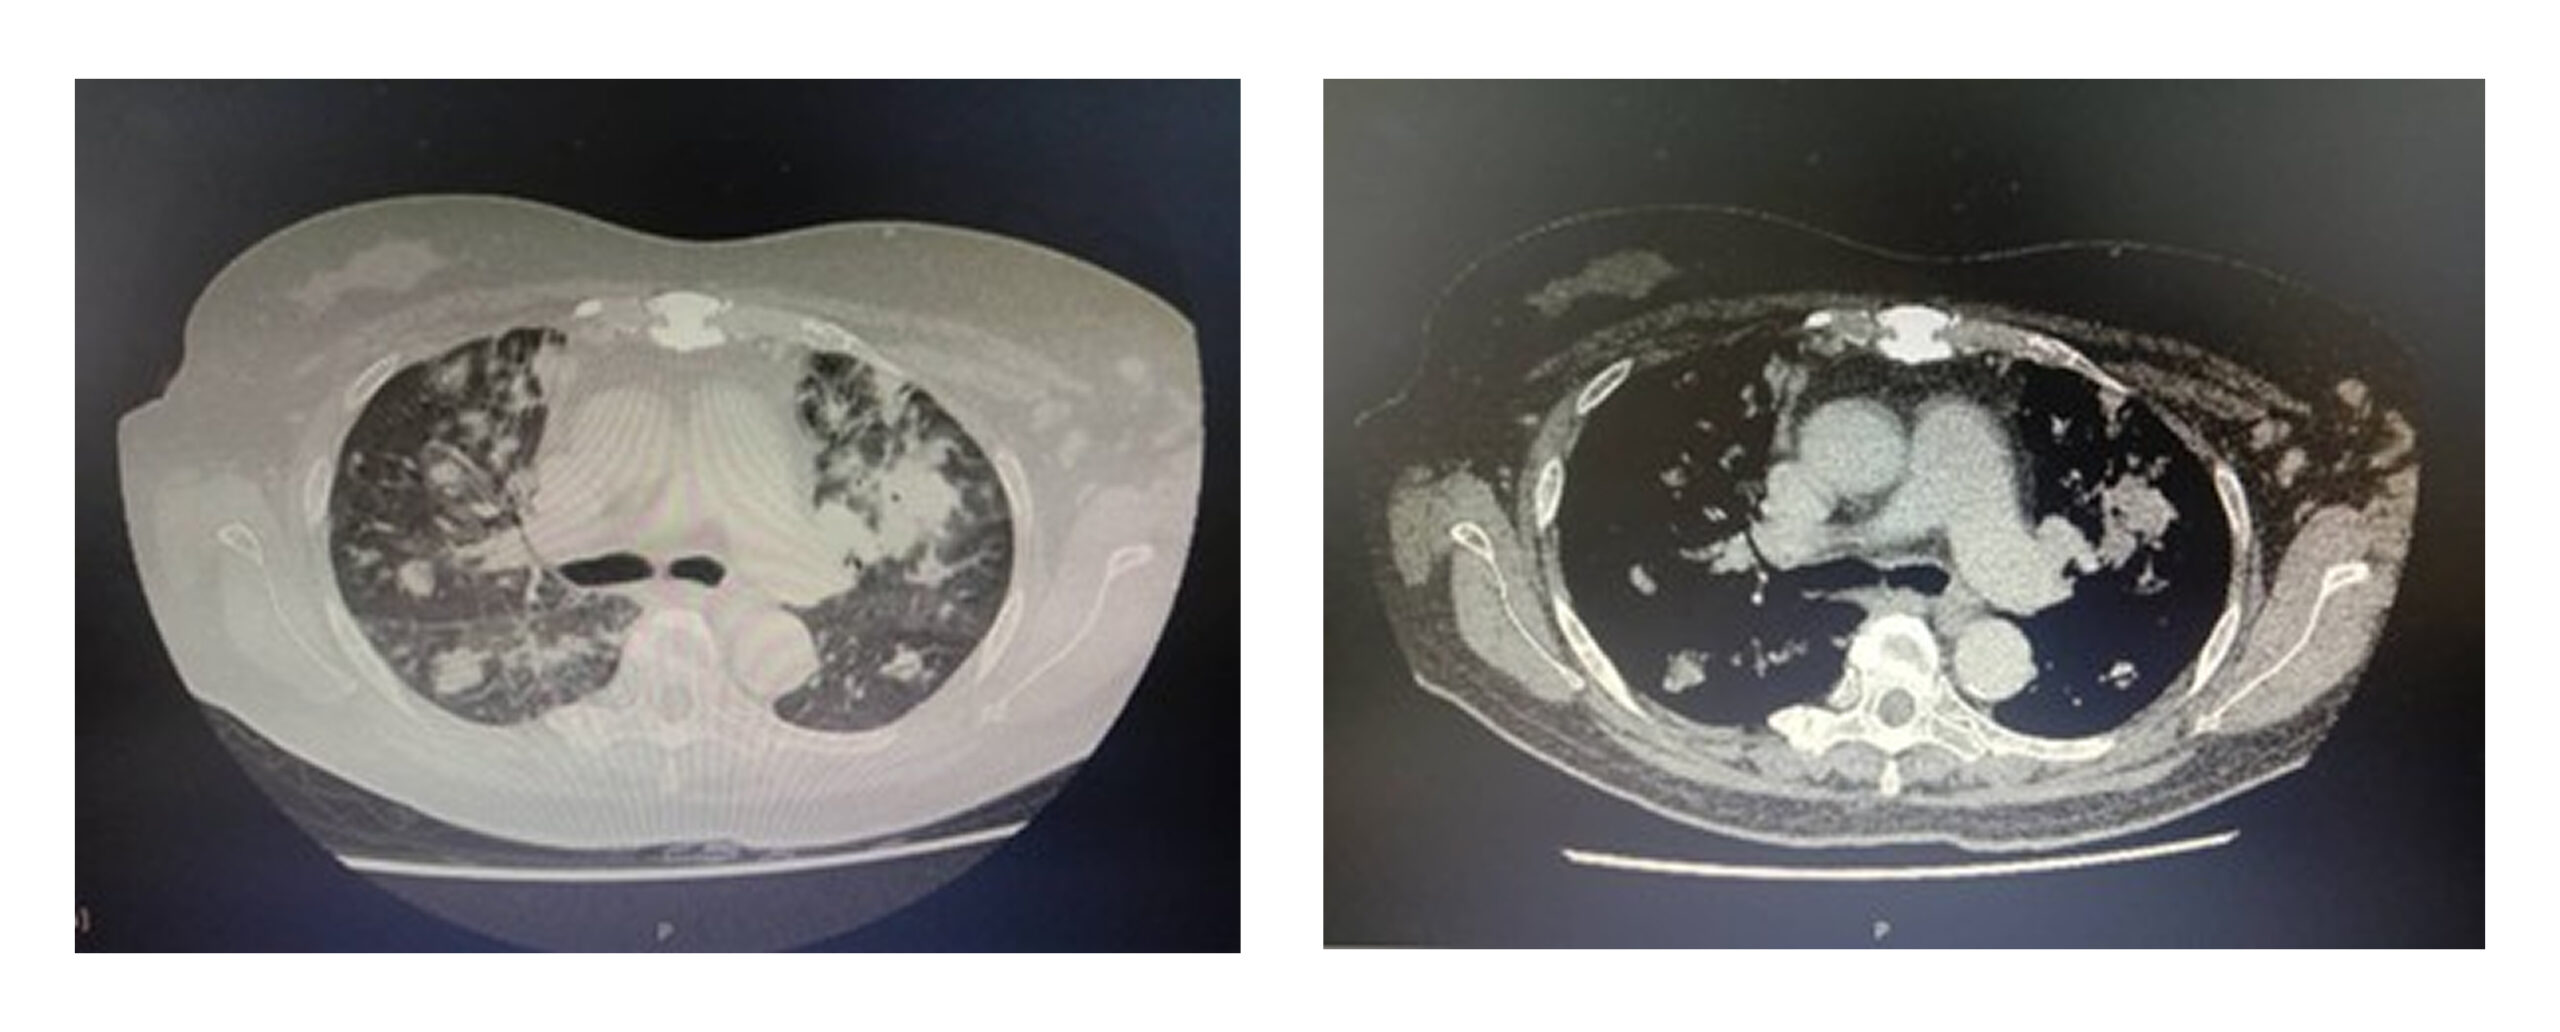

Contrast-enhanced computed tomography (CECT) of the thorax demonstrated multiple bilateral pulmonary nodules of varying sizes, some with irregular and lobulated margins. (Figure 2) Bronchoscopy appeared normal, and the bronchoalveolar lavage (BAL) was negative for M. tuberculosis on culture, direct smear, and polymerase chain reaction (PCR). BAL cytology was also negative for malignancy.

Figure 2: Multiple bilateral pulmonary nodules of varying sizes